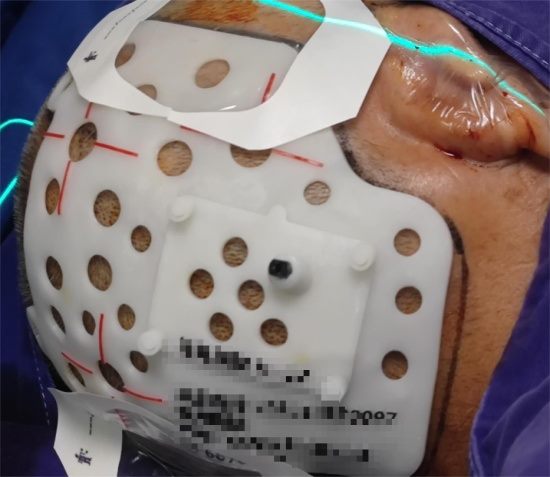

碘-125放射性粒子3D打印模版在颅脑肿瘤碘-125植入术

手术中